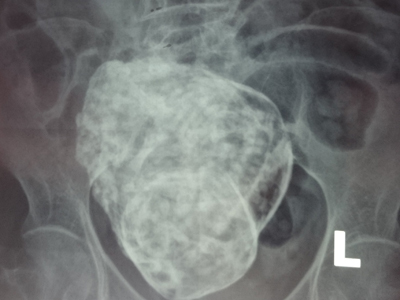

Theo Sở Y tế, hiện nay, toàn tỉnh có 917 người nhiễm HIV còn sống; số bệnh nhân AIDS là 548 người. Qua 10 năm triển khai, chương trình tư vấn, chăm sóc hỗ trợ và điều trị cho bệnh nhân HIV/AIDS ở tỉnh đã đạt được nhiều kết quả. Tỷ lệ tử vong do HIV/AIDS giảm từ 50% (năm 2004 - 2007) xuống còn 33% (từ năm 2008 đến nay); tỉnh Khánh Hòa không còn trong danh sách 10 tỉnh, thành trong cả nước có tỷ lệ người nhiễm HIV/AIDS cao; có 1.220 người nhiễm HIV/AIDS được lập hồ sơ quản lý sức khỏe, đã điều trị cho 747 người. Ngoài ra, toàn tỉnh đã thành lập 3 phòng khám ngoại trú HIV/AIDS...

Năm 2014, ngành Y tế đặt ra mục tiêu điều trị ARV cho 630 người lớn và trẻ em nhiễm HIV/AIDS; 75% phụ nữ mang thai được tư vấn, xét nghiệm HIV; 85% phụ nữ mang thai nhiễm HIV được điều trị dự phòng lây truyền từ mẹ sang con; 70% người nhiễm HIV mắc lao được điều trị đồng thời lao và HIV/AIDS...